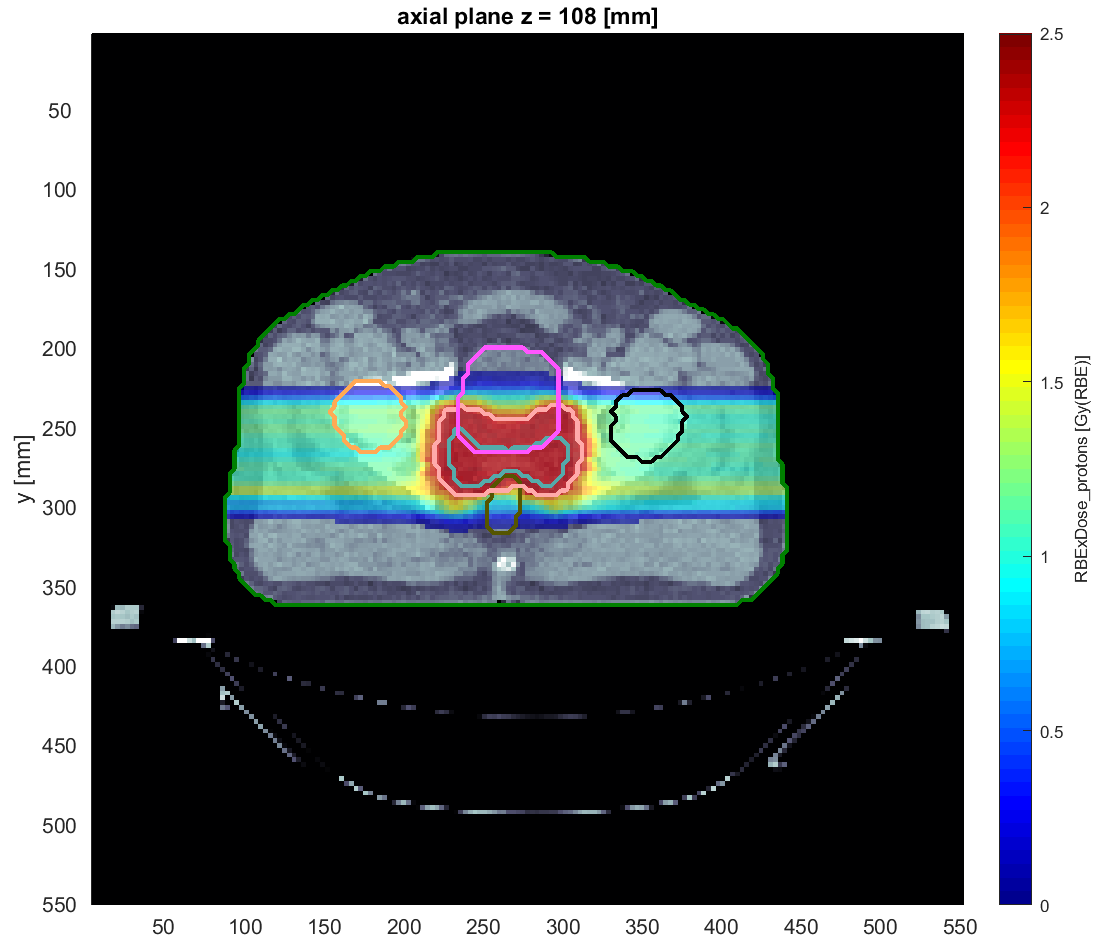

They have developed the matRad open source Treatment Planning System which is the basis for the Particle Therapy MasterClass education project.

Έχουν αναπτύξει το Σύστημα Σχεδιασμού Θεραπείας ανοιχτού κώδικα matRad , το οποίο αποτελεί τη βάση για το εκπαιδευτικό έργο Particle Therapy MasterClass για τη θεραπεία σωματιδίων.